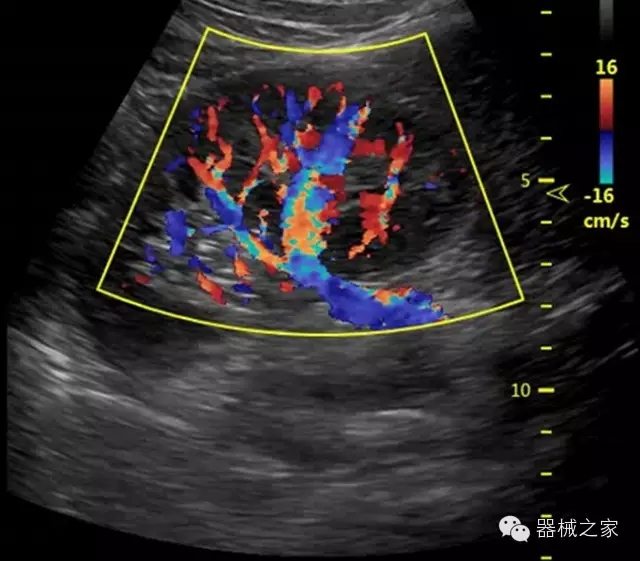

·智能微血流成像技術(shù):智能微血流捕捉技術(shù)可以提取出隱藏在背景噪聲中的弱血流信號,大大提高低速血流的敏感性;

·移植S40高端臺式彩超高端平臺技術(shù),滿足超聲科腹部、淺表、婦產(chǎn)科、心血管、肌骨等應(yīng)用,提供超聲科完美解決方案;

·IMT血管內(nèi)中膜自動測量:為血管性疾病評估提供了有效的評估手段;